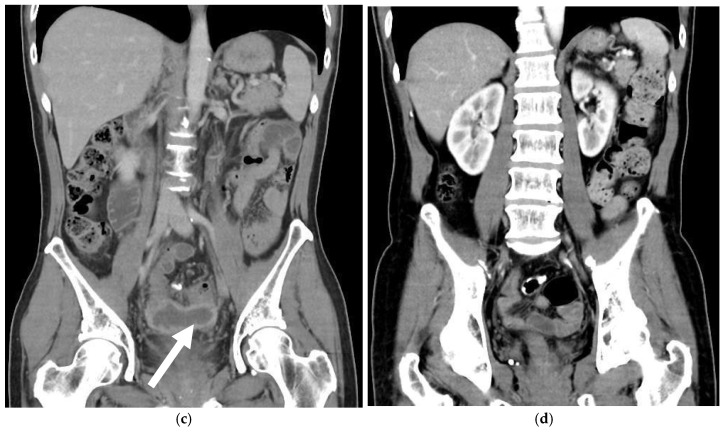

背景与目的:性别肯定手术可显著改善跨性别女性的生活质量和心理健康。在各种技术中,乙状结肠阴道成形术因其能够提供足够的阴道深度和内在润滑而被广泛应用。然而,它也有风险,新阴道穿孔是一种严重但未被报道的并发症。材料与方法:本文综述了新发阴道穿孔的病因、临床表现、诊断和治疗。我们进行文献回顾,分析报告的病例和治疗策略。此外,我们提出了一个来自我们机构的病例,以突出诊断和治疗方面的挑战。结果:新阴道穿孔是由机械损伤、缺血、感染或乙状结肠段结构缺陷引起的。常见的危险因素包括不适当的扩张、内径狭窄和血管损伤。症状从轻微的盆腔不适到腹膜炎和败血症。计算机断层扫描(CT)是诊断的金标准。轻微病例保守治疗有效,严重病例需手术修复。结论:新的阴道穿孔是罕见的,但可能危及生命。未来的研究应改进手术技术、扩张方案和组织工程解决方案。标准化指南和患者教育对于预防和改善结果至关重要。

Background and Objectives: Gender affirmation surgery significantly improves the quality of life and psychological well-being of transgender women. Among various techniques, sigmoid vaginoplasty is widely performed due to its ability to provide adequate vaginal depth and intrinsic lubrication. However, it carries risks, with neovaginal perforation being a serious yet underreported complication. Materials and Methods: This review examines the etiology, clinical manifestations, diagnosis, and management of neovaginal perforation. A literature review was conducted to analyze reported cases and treatment strategies. Additionally, we present a case from our institution to highlight diagnostic and therapeutic challenges. Results: Neovaginal perforation arises from mechanical trauma, ischemia, infection, or structural weaknesses in the sigmoid segment. Common risk factors include improper dilation, introital stenosis, and vascular compromise. Symptoms range from mild pelvic discomfort to peritonitis and sepsis. Computed tomography (CT) is the gold standard for diagnosis. Conservative management is effective in mild cases, whereas severe cases require surgical repair. Conclusions: Neovaginal perforation is rare but potentially life-threatening. Future research should refine surgical techniques, dilation protocols, and tissue engineering solutions. Standardized guidelines and patient education are essential for prevention and improved outcomes.